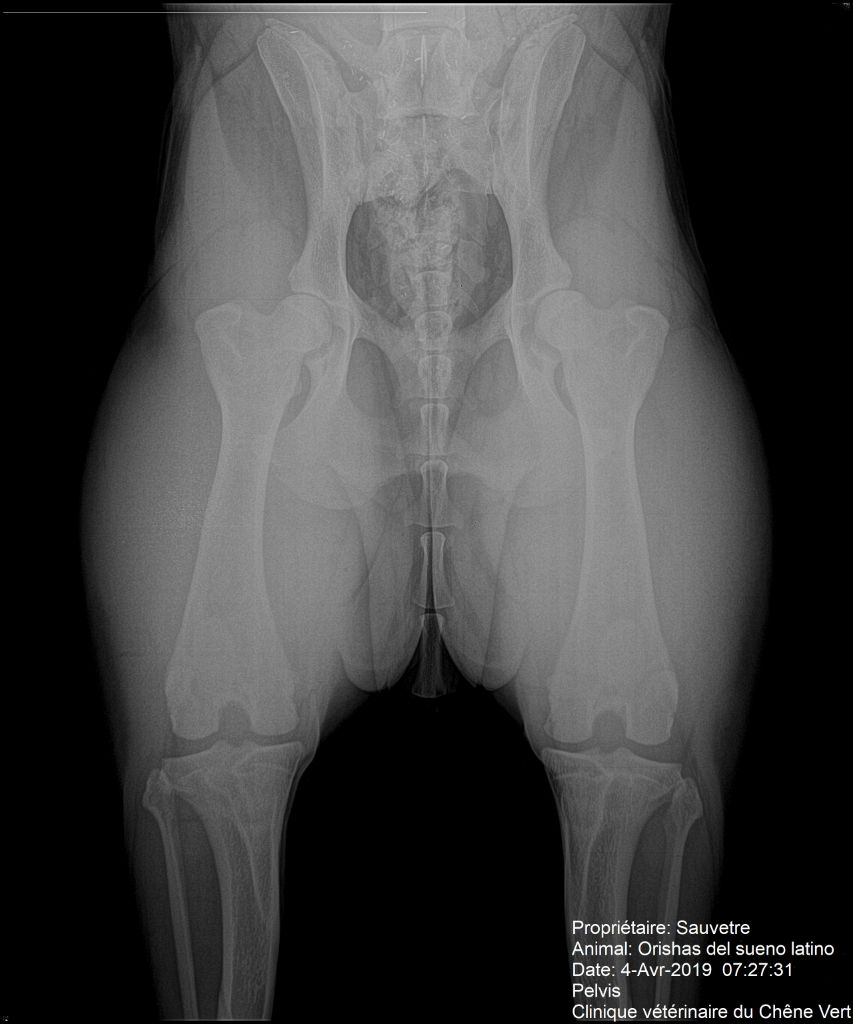

Radiographie des hanches

Compte rendu officiel - dysplasie hanches

Dysplasie coudes : : 0/0 officiel Dysplasie hanches : : A/B officiel PEA : : +/+ officiel |